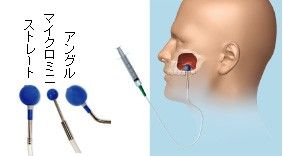

上顎骨と上顎洞とを隔てる上顎洞粘膜 バルーンリフトテクニック(上顎洞粘膜をリフトアップします)

以下の写真は 先日 行ったソケットリフト症例です。

サイナスリフト症例となるべく 骨の薄い部分も存在する症例であります。

黄色の線で書いた上顎洞底の粘膜( シュナイダー膜)を破らないようにしてリフトアップさせます。

上顎骨とシュナイダー膜の間に インプラント体(フィクスチャー)と 骨補填材(将来 骨に置換され

るものです)を入れていきます。

バルーンリフトテクニックは使用しておりませんが、リフティングドリルと骨補填材の使用により、